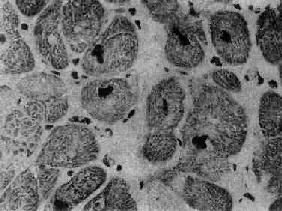

肥厚性心肌病

图8-37 肥厚性心肌病

心肌细胞排列紊乱 ×180(原放大)(采自Edwards)